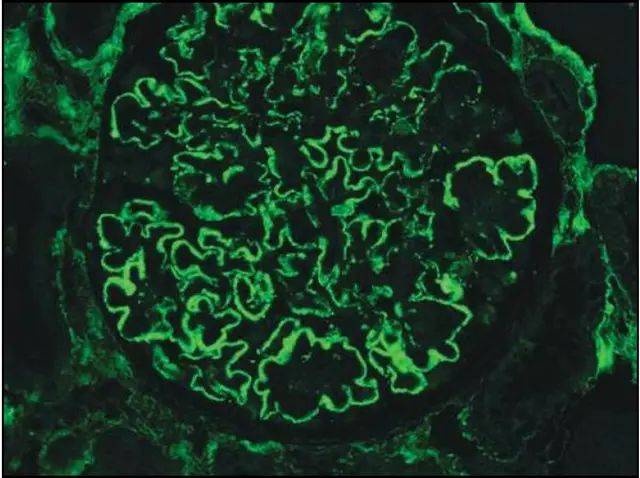

肾内病理图解 | 膜性肾病

肾内病理图解 | 膜性肾病